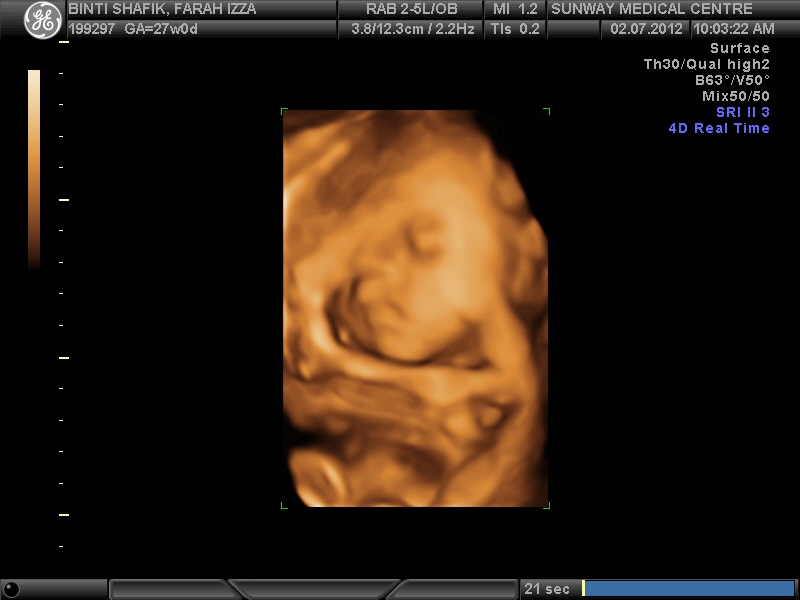

Alhamdulilah adik dah menjangkau 27 weeks so tak lama lg dah masuk ke third trimester.... :) Rase cam baru2 jeks lg discover yang I preggie *sobs* --> happy tears....

susah tuh nk aim.. sebab mamat ni suke letak tangan kat atas muke...

tak pun gosyok2 muke kat uri... jadikkan bantal peluk dia...

see~~ selesa sungguh tido kat dlm perut... saya dah kenyang...

langsung tido.... dan tido... selama sejam ni jeks la gambo yg dpt di amik...